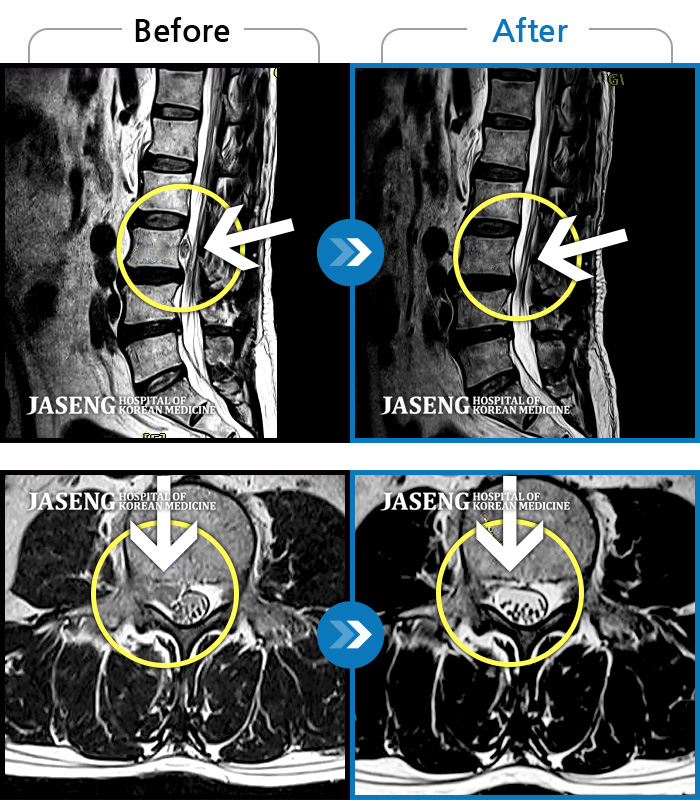

MRI 치료사례

우측 허리부터 골반 통증, 우측 다리까지 이어지는 저림감, 10분이상 앉아있기 어려움